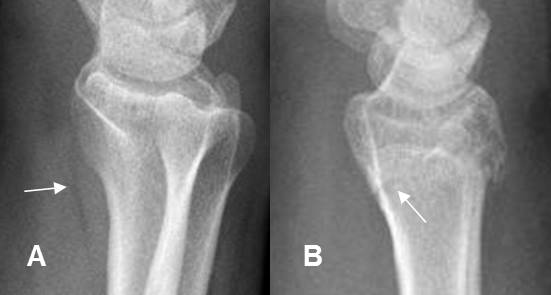

Fig 17. Hemartrosis.

A: Rx AP. Fracturas no desplazadas, ni deprimidas en los platillos tibiales.

B: Rx lateral con rayo horizontal. Nivel grasa/líquido en la región suprapatelar, por hemartrosis.